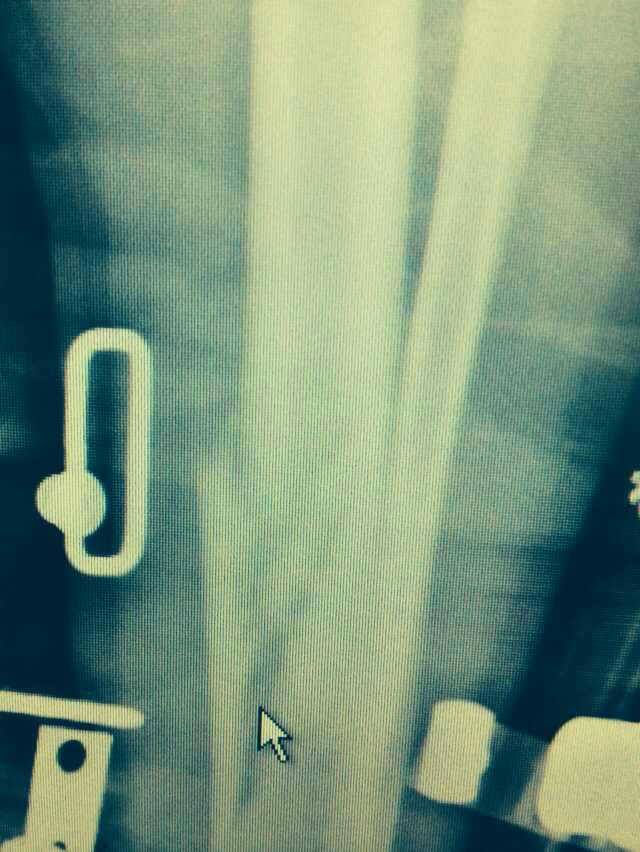

【byb.cn 】(來(lái)源:綜合)2014年12月18日,現(xiàn)年57歲的著名體育評(píng)論員韓喬生,在崇禮云頂滑雪場(chǎng),騎行德國(guó)雪上自行車(chē)的時(shí)候,因速度太快,控制不住,韓喬生為避免沖下路基,與一滑行單板的美女相撞,美女因裝備厚,無(wú)大礙,韓喬生則導(dǎo)致左腿脛骨、腓骨兩外骨折,后已經(jīng)被緊急送往北京的醫(yī)院治療。